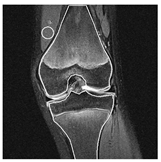

| Patient | Patient ID | Image Label | Image Prediction | Original Image | High Intensity Masking Image |

|---|---|---|---|---|---|

| Edema | 21 | Edema | Non-edema | ![]() | ![]() |

| Edema | 21 | Non-edema | Edema | ![]() | ![]() |

| Non-edema | 2 | Non-edema | Edema | ![]() | ![]() |

| Non-edema | 5 | Non-edema | Edema | ![]() | ![]() |

| Non-edema | 20 | Non-edema | Edema | ![]() | ![]() |

| Non-edema | 30 | Non-edema | Edema | ![]() | ![]() |